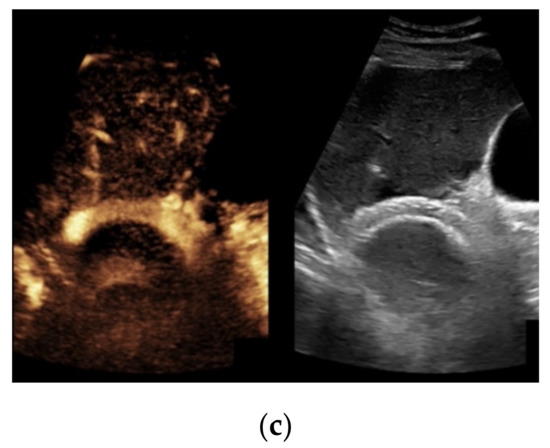

Figure 4. Same patient as in Figure 1 with continuous flow within the transjugular intrahepatic portosystemic shunt (TIPS) without thrombosis or occlusion using microflow imaging (a) and after administration of contrast agent (b,c).

Based on initial findings from CDUS, 67% (n = 71) of the patients showed normal perfusion within the TIPS (Figure 1). 18% (n = 19) of the cases presented stent occlusion (Figure 2) while 6% of the patients (n = 6) had partial occluding stent thrombosis (Figure 3). The TIPS perfusion in five patients was only partially assessable, while in two patients an examination was not feasible due to extensive meteorism. The patients listed under “others” showed postoperative entrapped air between the wall of the vessel and the stent (n = 2) while one patient had two TIPS, one occluded and one with a normally detectable blood flow (Table 1).

When taking a closer look at the results of the CEUS examinations, 70.8% (n = 75) of the patients showed regular stent perfusion (Figure 4), 17.9% (n = 19) of the patients featured TIPS occlusion (Figure 5) while 6.6% (n = 7) patients had stent thrombosis (Figure 6). In contrast to the results from CDUS, there were no patients with only partial accessibility of the TIPS during CEUS, while the two patients with meteorism also were not assessable during CEUS. The three patients categorized in “others” showed simultaneous findings between CDUS and CEUS (Table 2).